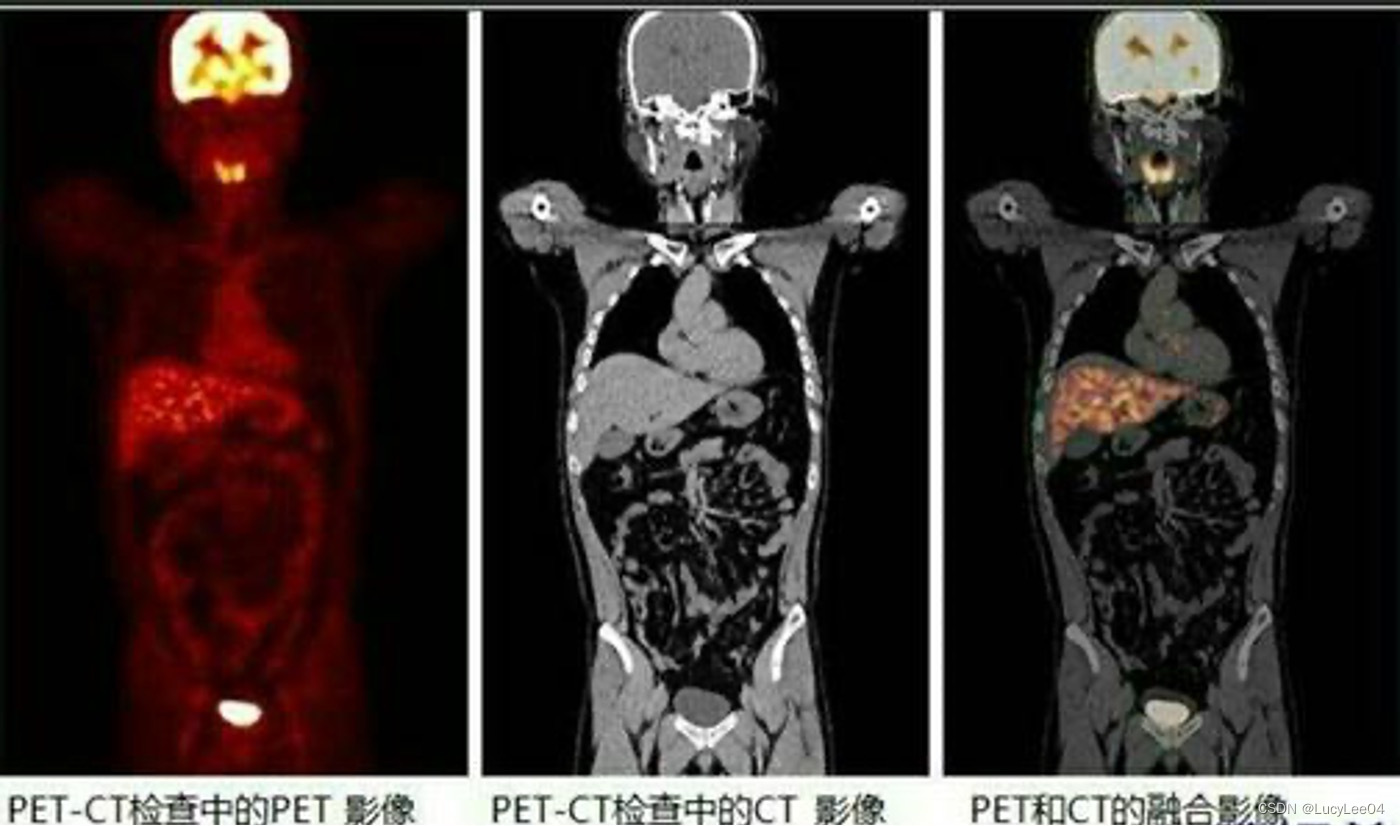

图像的正确重建与可视化

多模态扫描图像的配准